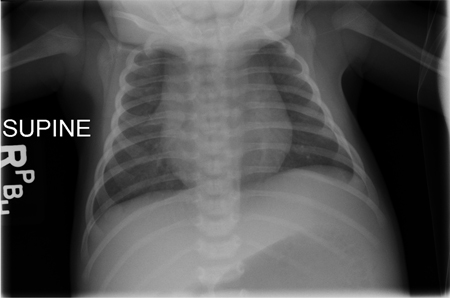

Demonstra ausência da sombra tímica em todos os pacientes com IDCG (exceto naqueles com IDCG devida a deficiência de coronina 1A).[40][4][Figure caption and citation for the preceding image starts]: Radiografia torácica de um bebê ilustrando a ausência de sombra tímica; os bebês com imunodeficiência combinada grave (IDCG) podem ser atímicos no momento da apresentaçãoChildren's Hospital of Wisconsin, Departamento de Radiologia; usado com permissão [Citation ends].com.bmj.content.model.Caption@7d493e0d[Figure caption and citation for the preceding image starts]: Radiografia torácica de um bebê ilustrando uma sombra tímica normalChildren's Hospital of Wisconsin, Departamento de Radiologia; usado com permissão [Citation ends].com.bmj.content.model.Caption@37fb11aa Esta observação dá suporte ao diagnóstico de IDCG.[4]

Os pacientes com IDCG por deficiência de adenosina desaminase podem demonstrar anormalidades costais anteriores à radiografia (isto é, escavação/desgaste das articulações costocondrais).[41]

Resultado

ausência de sombra tímica (exceto na IDCG por deficiência de coronina 1A) ou anormalidades nas articulações costocondrais